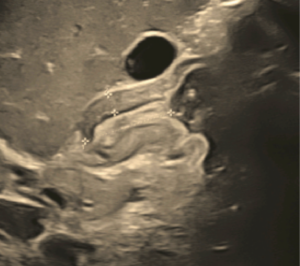

Con la sospecha clínica de estenosis hipertrófica de píloro, se solicita estudio ecosonográfico, el cual se observa en forma clara la imagen característica de la elongación del píloro, con aumento del grosor del componente muscular del píloro. El informe consta de los siguientes datos: -Hígado de ecogenicidad, forma y tamaño normal. -Vesícula biliar de paredes delgadas, sin ecos internos, no existe dilatación de vías biliares. -Riñón derecho de forma normal. -Engrosamiento de la pared muscular a nivel del píloro, que medido en el centro del canal pilórico tiene un espesor de 3.7 mm y una longitud del canal de 17 mm. -Estómago se halla distendido con contenido alimenticio y aire, retraso en el vaciamiento gástrico en el estudio dinámico.

La clínica del padecimiento conforma una tríada distintiva (vómitos postprandiales violentos, ondas peristálticas de lucha y oliva palpable) que permite el diagnóstico en el 90% de casos 1 3. La ecografía abdominal con sensibilidad de 90-99% y especificidad de 97-100%, en manos expertas, confirma el diagnóstico 1 2 3. La imagen ecosonográfica clásica es aumento del grosor de la musculatura (normal 2 mm) y alargamiento del canal pilórico (normal 12 mm) 1 4 5 6. El uso de bario para un estudio de contraste, la endoscopía digestiva alta, son posibilidades para determinados casos 4 6. El laboratorio, en algunos casos, determinará una alcalosis metabólica hipoclorémica hipokalémica, resultado de la pérdida de cloro en los vómitos y aumento de la concentración de bicarbonato; y la consecuente retención de hidrogeniones por el riñón en detrimento del potasio 1 3 7. Es posible el aumento de la bilirrubina indirecta por disminución del paso del estómago al duodeno, con incremento de la circulación enterohepática.